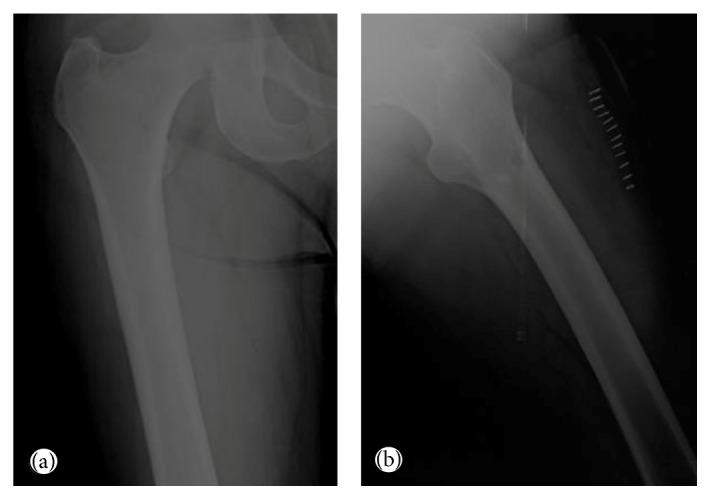

We describe an unusual case of hairy cell leukemia (HCL) in a 55-year-old male presenting with isolated skeletal disease as the initial manifestation without abnormal peripheral blood counts, bone marrow involvement, or splenomegaly. To the best of our knowledge, there have been only two previous reports of a similar case. The patient presented with pain in the right femur. Anteroposterior radiographs of both femurs revealed mixed lytic-sclerotic lesions. PET scan showed multiple metastatic lesions on axial skeleton, pelvis, and both femurs. Histopathological examination of the bone biopsy revealed an infiltrate of HCL. Localized radiation therapy to both proximal femurs and subsequently 4 weeks later, a 7-day course of 0.1 mg/kg/day cladribine provided complete remission with relief of symptoms and resolution of bone lesions. We addressed the manifestations and management of HCL patients with skeletal involvement.

我们描述了一例罕见的毛细胞白血病(HCL)病例,患者为一名55岁男性,最初表现为孤立性骨骼疾病,外周血细胞计数正常,无骨髓受累或脾肿大。据我们所知,此前仅有两篇类似病例的报道。该患者表现为右股骨疼痛。双股骨前后位X线片显示溶骨性硬化混合性病变。PET扫描显示中轴骨骼、骨盆和双股骨有多处转移灶。骨活检的组织病理学检查显示有HCL浸润。对双侧股骨近端进行局部放射治疗,4周后,给予0.1mg/kg/天的克拉屈滨,疗程7天,症状缓解,骨病变消退,实现完全缓解。我们探讨了骨骼受累的HCL患者的表现及治疗。